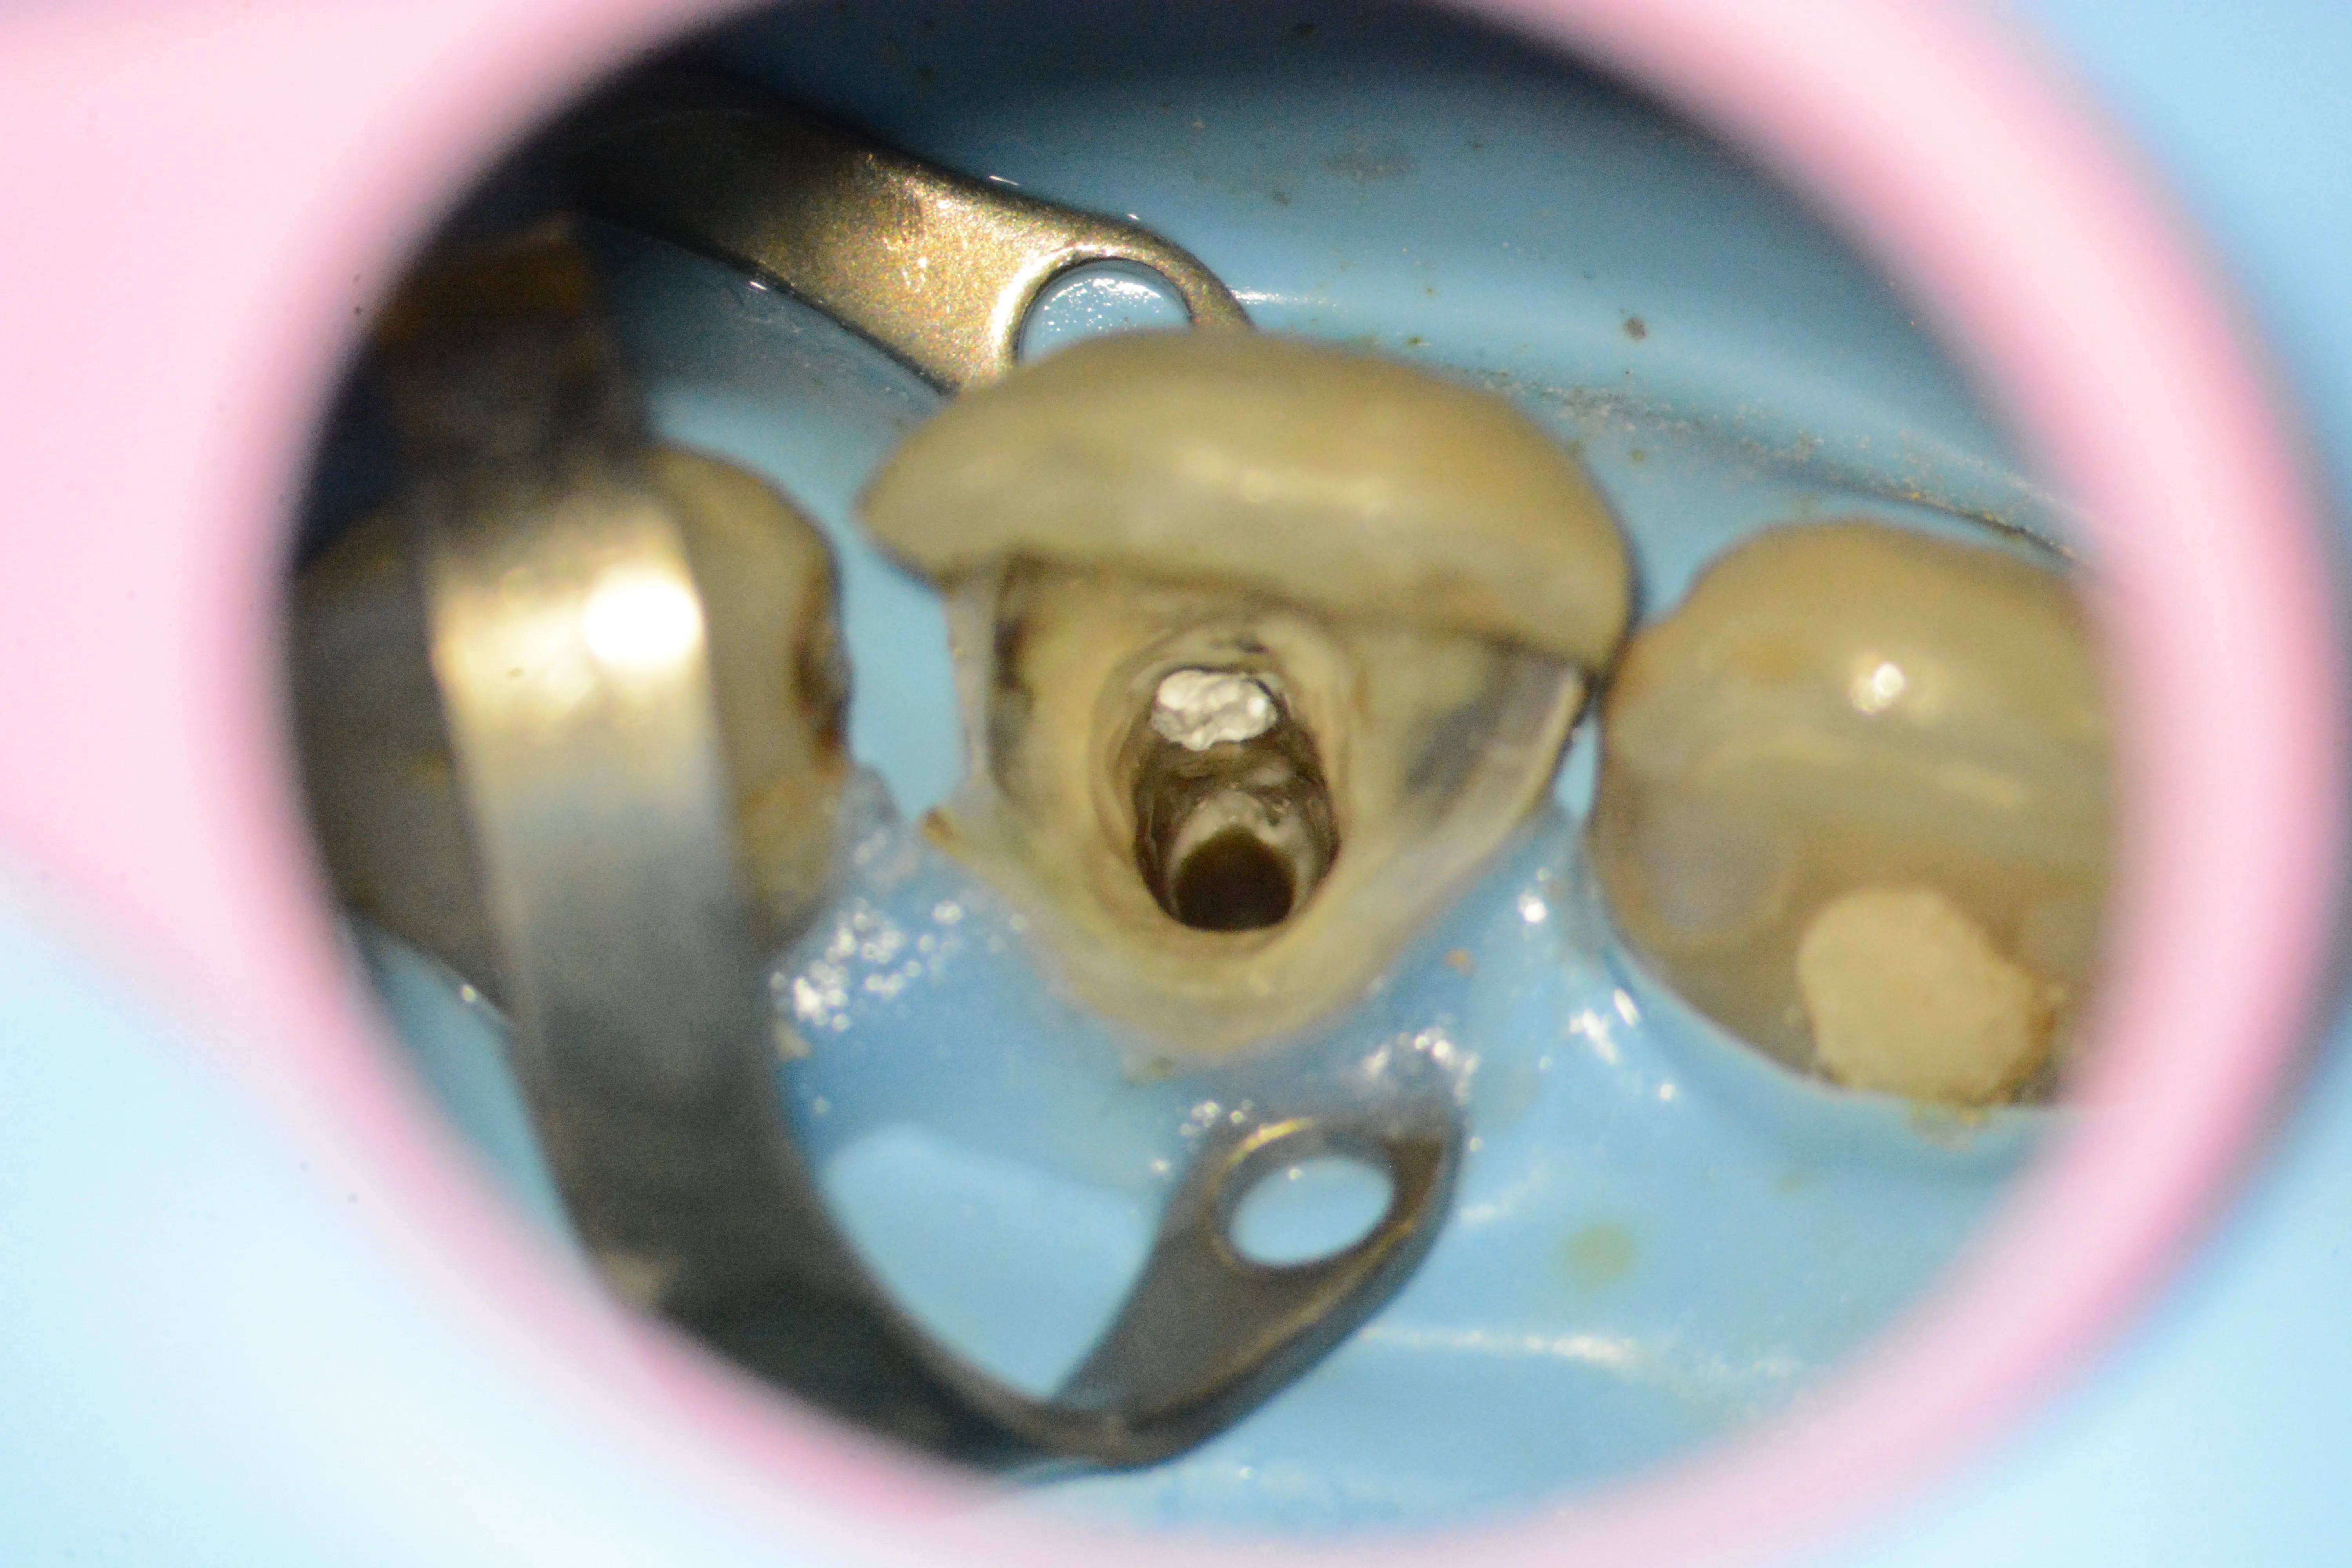

7 – Expunerea frezei pentru a încerca mobilizarea ei

8 – Freza fracturată îndepărtată